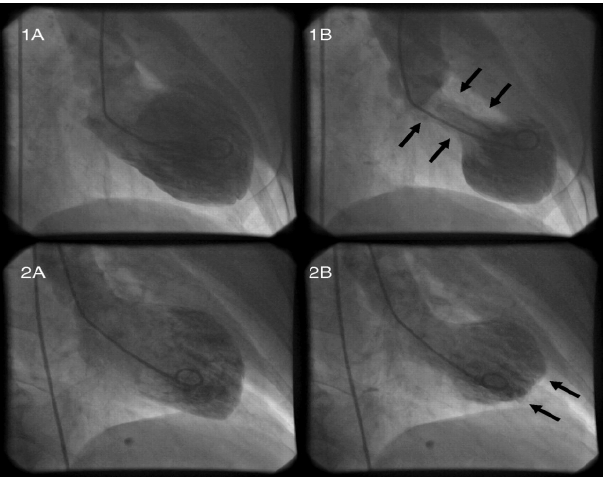

Mulher 55 anos, hipertensa, após a morte de seu filho evolui com dor torácica em aperto com irradiação para braço esquerdo. Ao procurar atendimento médico, realizou exames que evidenciaram níveis de troponina elevados e seu eletrocardiograma foi normal. Levada ao cateterismo, observa-se que suas coronárias eram normais, porém havia alteração de seu ventrículo. Este estava com hipocinesia, médio e apical associada a hipercinesia compensatória basal.

Qual provável diagnóstico desta paciente: